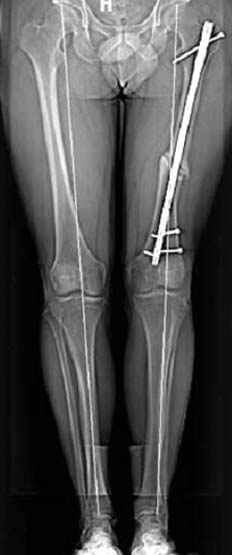

Если, например, доводится лечить больных с псевдартрозами шейки бедра, то надобность есть, и приходится. См. приложение.

Несколько снимков из моей коллекции, чтобы разьяснить, почему мы до сих пор делаем различные варианты остеотомии.

На рисунке N1 предоперационный план лечения ложного сустава шейки бедра- линия ложного сустава, угол и направление введения импланта, клиновидная остеотомия в градусах и миллиметрах, второй снимок после коррекции, расчет, на сколько удлиняется конечность и размеры импланта;

N3 рисунок окончательный снимок, после операции моя рентгенограмма должен выглядеть примерно как эта картина. На N4 снимке клин перед удалением; N5 послеоперации 3 нед.; N6 окончательная рентгенограмма.

варус при проксимальном отделе 95 градусной пластиной.

Отправитель: Djoldas Kuldjanov 23 Ноябрь 2004, 18:21

пластическая модель; и коррекция бедра аппаратом Илизарова.